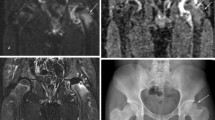

One observer (YJK) blinded to the MR imaging findings, graded the radiographic stage of the hips at the time of MR imaging. The original Waldenström classification [28] described the evolution period (initial and fragmentation stages), healing period, growing period (healed femoral epiphysis with open physis), and definite period (closed physis). We used a modified Waldenström classification to grade the radiographic stage: initial stage (eight patients), fragmentation stage (six patients), healing stage (two patients), and residual stage (one patient). The grading was confirmed by another independent observer (WJY). One pediatric radiologist (JEC) assessed the signal intensity (SI) of the epiphysis and the metaphysis of the femoral head on T2-weighted images as increased, similar, or decreased when compared with the contralateral normal side (control), and investigated focal physeal irregularities (increased undulation, interruption, and/or cystic changes of the physis) using intermediate-weighted and spoiled gradient echo images. Based on observational findings in perfusion MR imaging [12], we determined the epiphyseal reperfusion pattern to be either transphyseal (enhancing vessels entering the epiphysis across the physis) or periphyseal (enhancing vessels entering the epiphysis lateral or medial to the physis).

Diffusion-weighted MR imaging revealed ischemic damage of the femoral head in all hips with LCP (Table 1). Epiphyseal ADC values were greater (p = 0.005) in the LCP hips than in the control hips. Metaphyseal ADC values also were greater (p = 0.006) in the LCP hips than in the control hips. For the LCP hips, epiphyseal ADC values increased early in the initial stage and remained elevated greater than 35% over the control side in all but one patient in the residual stage (Fig. 3). In all patients, gadolinium-enhanced imaging showed areas of decreased contrast enhancement in the marrow of the secondary ossification center. The metaphyseal ADC values also increased in all hips in the initial and fragmentation stages, with wider variations than in the epiphyseal ADC values (Fig. 4): only six of the 17 patients (35%) had an ADC ratio greater than 50% in the metaphysis.

Diffusion changes in the metaphysis were associated with a reperfusion pattern to the epiphysis, increased SI in the metaphysis, and focal physeal abnormalities. Epiphyseal reperfusion patterns, based on observational findings in perfusion MR imaging, were periphyseal in nine patients (Fig. 5) and transphyseal in eight (Fig. 6). Increased metaphyseal diffusion tended to be associated with (p = 0.05) transphyseal pattern of reperfusion to the epiphysis: metaphyseal ADC values greater than 50% over the control side (ADC ratio > 50%) had 13 times greater odds of being associated with transphyseal reperfusion to the epiphysis. The metaphyseal ADC ratio greater than 50% also was associated with an increased T2-signal intensity of the metaphysis (p < 0.001) and the presence of focal physeal irregularity (p = 0.035) (Table 2).

The MR images of a 2-year 11-month-old boy with LCP of the left hip are shown. The (A) ADC map and a (B) gadolinium enhanced fat-suppressed T1-weighted image of the right hip (control side) were compared with a (C) gadolinium enhanced fat-suppressed T1-weighted image of the left hip showing periphyseal reperfusion (arrows) in the epiphysis and the (D) ADC map of the left hip showing increased diffusion to the epiphysis.

The MR images of a 6-year-old boy with LCP of the left hip are shown. The (A) ADC map and a (B) gadolinium enhanced fat-suppressed T1-weighted image of the right hip (control side) were compared with a (C) gadolinium enhanced fat-suppressed T1-weighted image of the left hip showing transphyseal reperfusion (arrows) to the epiphysis and (D) the ADC map of the left hip showing increased diffusion to the epiphysis and the metaphysis.